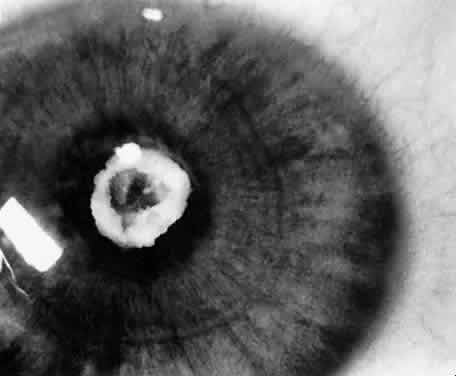

Usually, anterior polar cataracts are visually insignificant and allow normal visual development (see Fig. 1). However, some affect vision, and all require careful monitoring.7 Centrally located cataracts that are on or near the posterior lens capsule have a greater effect on the refraction of light and visual acuity (Fig. 2). Nuclear cataracts associated with metabolic disorders or prenatal infections produce double refracting systems that cause optical distortion and significantly decrease visual acuity (Fig. 3).

Progression

Not all cataracts in children increase in size or density. Premature neonates may have partial opacification (transient neonatal opacities) that may disappear over the first 1 or 2 weeks of life.8 Other cataracts that may regress are those due to galactosemia. These cataracts have the morphologic features of oil droplets. If early dietary restriction of galactose is observed, the opacity may regress.9 Anterior polar cataracts typically remain stable in size and density.